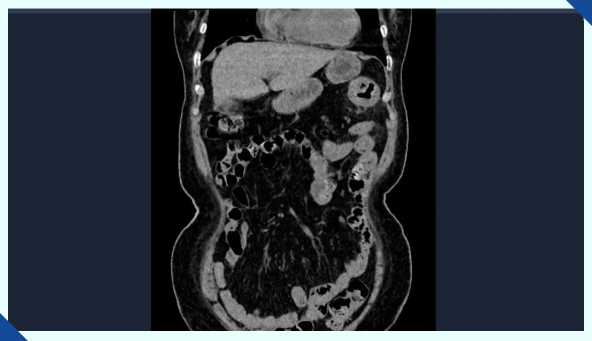

在进一步的全腹部CT检查中,医生发现李阿姨脾区存在占位性病变。按照常规经验,脾区肠道出现问题往往会伴随便血症状,但李阿姨却坚称自己从未出现过这种情况。消化内科的吕后宁主任没有轻易下结论,而是耐心地追问起她的排便情况。这时,李阿姨才想起,自己最近一段时间大便颜色发黑,但一直以为是长期喝中药导致的,根本没往肠道疾病上想。正是这个被忽视的“黑色信号”,让病情一拖再拖,直到贫血症状严重才引起重视。

经无痛肠镜检查,吕主任发现李阿姨脾区肠壁增厚,肠道已经出现狭窄,肠镜无法顺利通过。随后取肿物进行活检,最终确诊为结肠癌。这个结果给李阿姨和她的家人敲响了警钟,也让我们深刻意识到,肠道发出的一些看似不起眼的信号,可能隐藏着致命的危机。